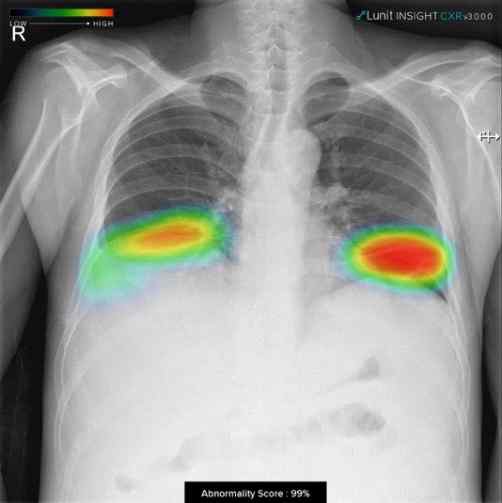

식약처는 지난 4월 제1호 혁신의료기기소프트웨어 제조기업으로 ㈜뷰노를 인증한데 이어 소프트웨어 품질 향상 체계와 개발 프로세스 성과 등이 우수한 ㈜루닛(제2호)과 ㈜코어라인소프트(제3호)를 추가로 인증했습니다.